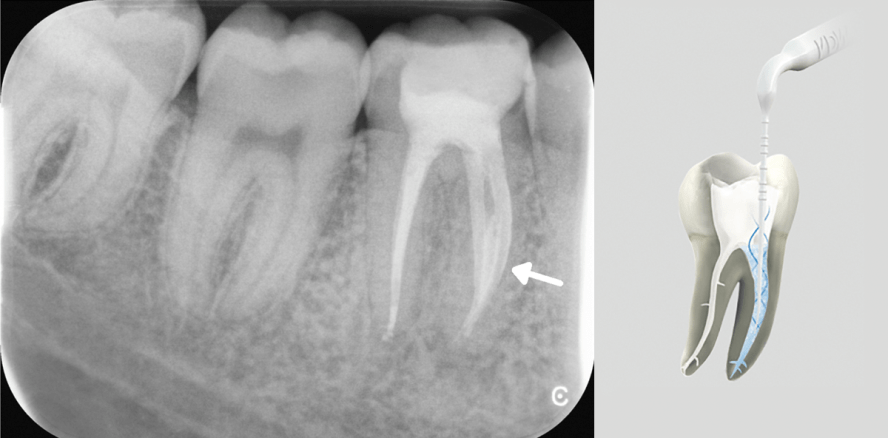

Um den Erfolg einer endodontischen Maßnahme langfristig gewährleisten zu können, muss eine vollständige chemomechanische Desinfektion des...

Um den Erfolg einer endodontischen Maßnahme langfristig gewährleisten zu können, muss eine...